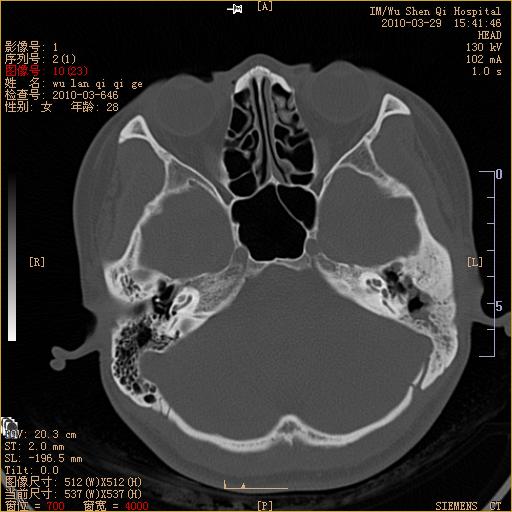

标题: CT25398:女,左耳流脓两年余,带有异物 [打印本页]

标题: CT25398:女,左耳流脓两年余,带有异物

左侧中耳乳突炎,不排除胆脂瘤形成。

左侧中耳乳突炎,胆脂瘤形成。

1)左侧慢性中耳乳突炎并肉芽肿(或胆脂瘤)形成。2)考虑左侧颞骨慢性炎症伴骨质增生硬化,不排除骨纤。